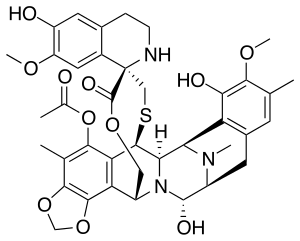

Trabectedin is composed of three tetrahydroisoquinoline moieties, eight rings including one 10-membered heterocyclic ring containing a cysteine residue, and seven chiral centers.